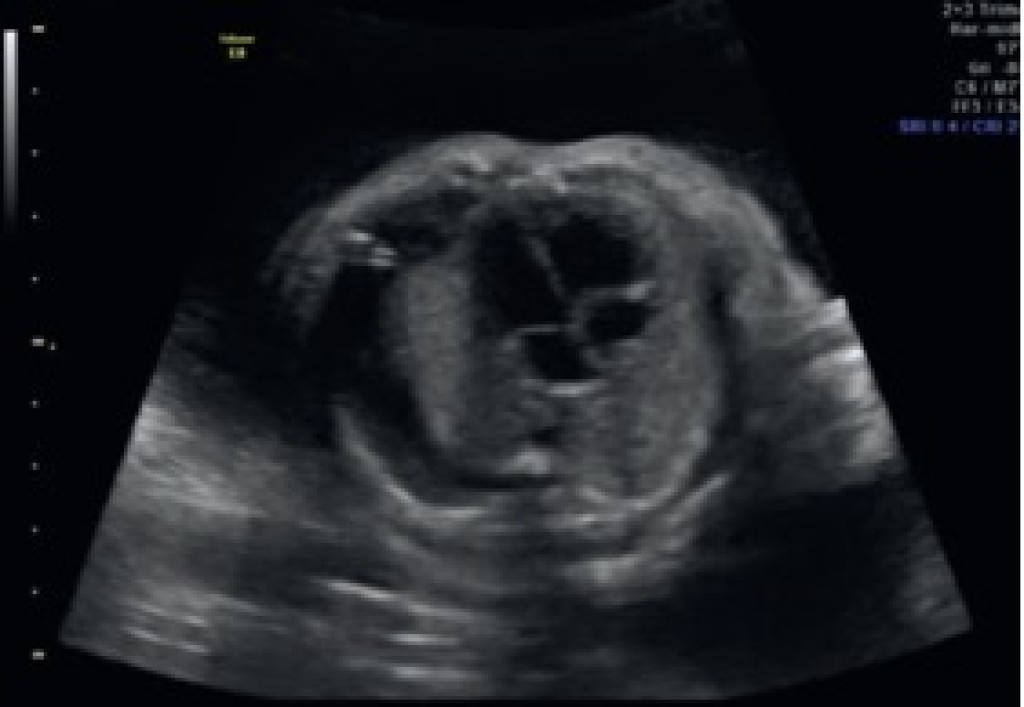

Fetal pleural effusion – before and after fetal intervention:

- Fetal thoracentesis – In this minimally invasive, ultrasound-guided procedure, a thin needle is placed through the mother’s uterus and into the fetal chest to draw out the fluid. During the procedure, a sample of chest fluid and amniotic fluid may be obtained for testing to help determine the cause of the pleural effusion and identify any other fetal conditions or abnormalities.

- Evaluate the fetal lungs for re-expansion, following thoracentesis.

- Watch for rapid buildup of fluid again – If the fluid quickly reaccumulates, determine if a shunt (drainage tube) would be beneficial to prevent repeated buildup, especially if it is early in the pregnancy.

- Thoracoamniotic shunting – Under ultrasound guidance, a small plastic tube, known as a shunt or catheter, is placed in the fetal chest, with one end in the chest cavity and the other end extending out into the amniotic cavity, enabling continual drainage of the pleural fluid. This is known as a “double pigtail catheter” (Rocket or Harrison shunt).

By draining the accumulated fluid, fetal interventions can reduce the pressure against the fetal lungs and heart, improving lung development, heart function and fetal outcomes.